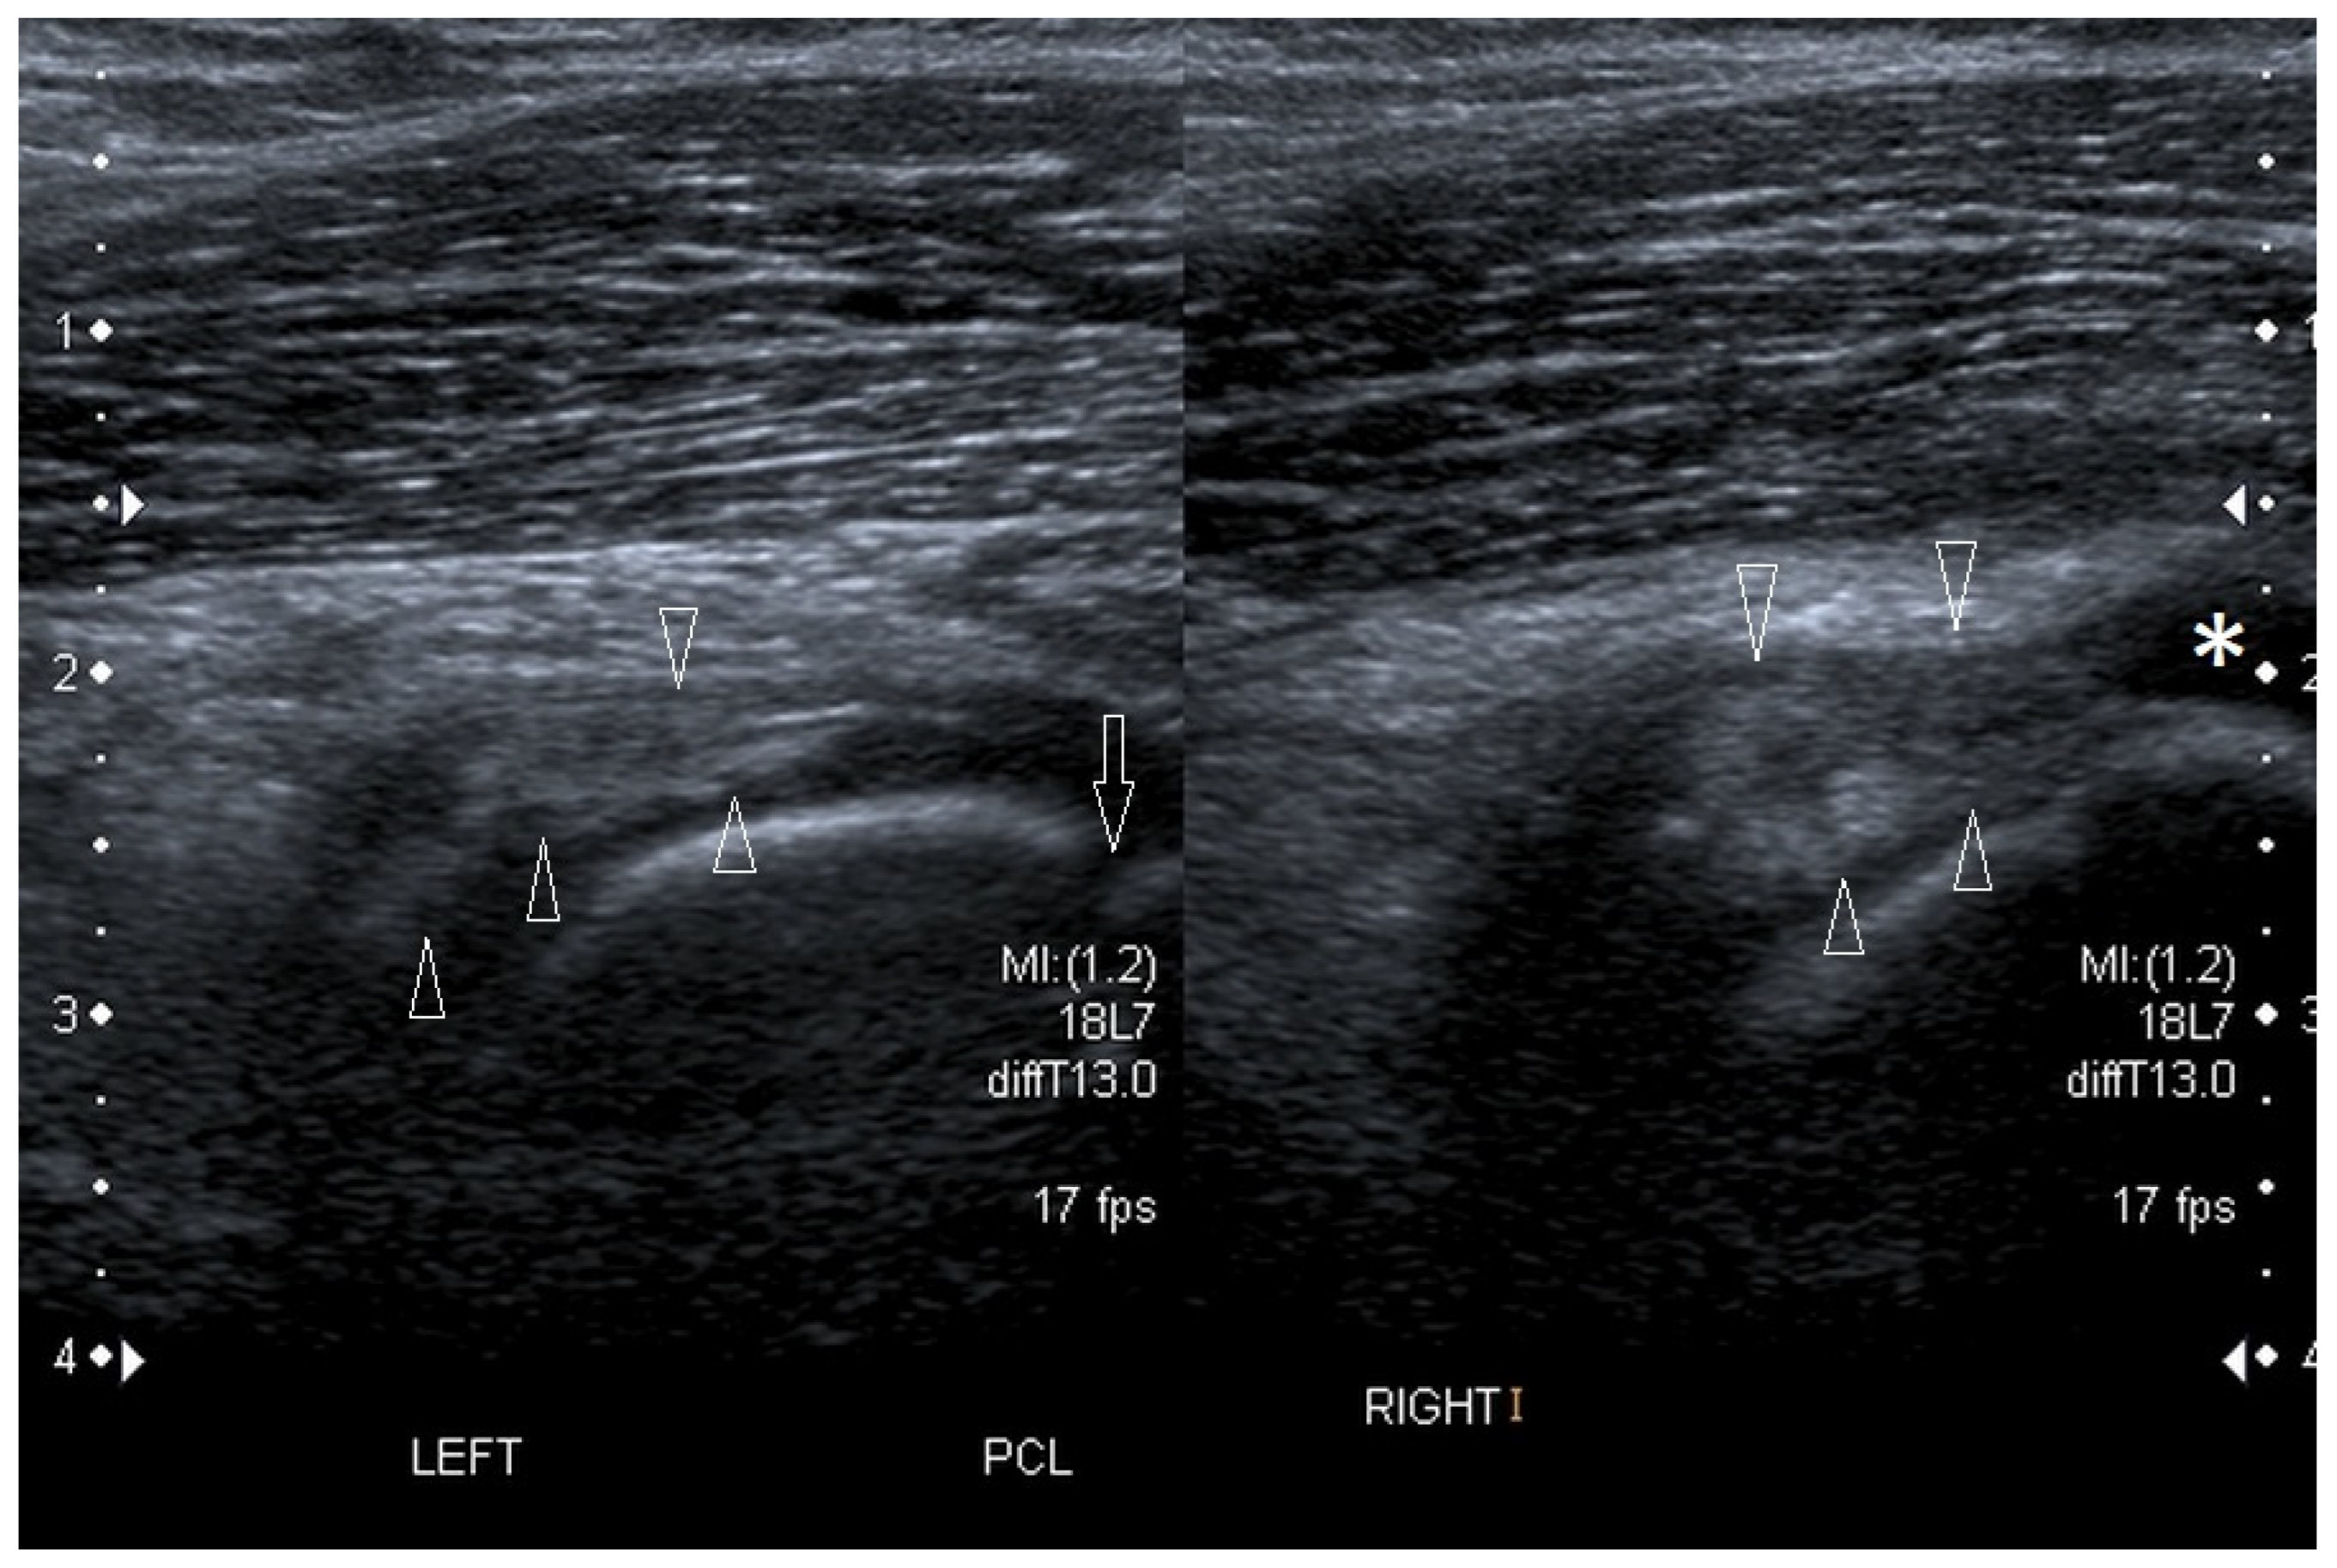

3.2.3. Ligament Injuries